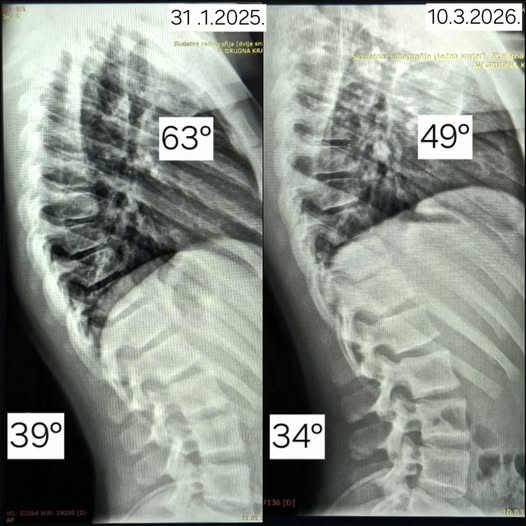

Prikazujemo rezultate jednogodišnje rehabilitacije hiperkifoze kod petnaestogodišnjaka.

Kombinacija manualne terapije, specifičnih vježbi po Schrothu i DNS principu. Rad s djetetom ne uključuje samo rad dok je dijete na terapiji, nego i procjenu, prikupljanje podataka, nalaza, dijagnostičkih snimki, promišljanje o planu i programu te evidencija svega navedenog.